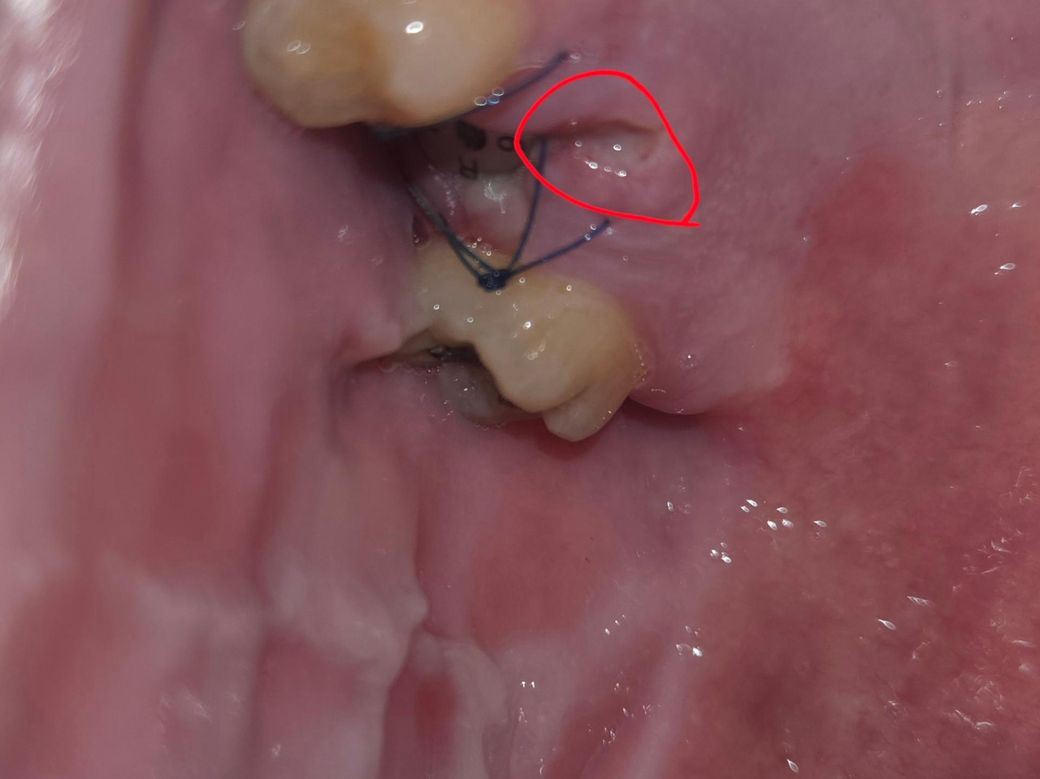

임플란트 5일차 봉합부위 벌어진건가요?

사진 빨간색 동그라미 부분 봉합이 벌어진건가요?

5일차가 되면서 땡기는 느낌이 강해져서 핸드폰으로

찍어보니 저런 구멍이 있어서요

그리고 고여있는 것 같은 하얀색은 염증인지도 궁금합니다

사진상으로느 봉합부위가 벌어졋거나 그런건 엇는거 같습니다. 크게 걱정은 안하셔도 될것같습니다.

봉합된 부위가 약간 벌어져있더라도 시간이 지나면 자연스레 회복되며 하얀색은 상피입니다.